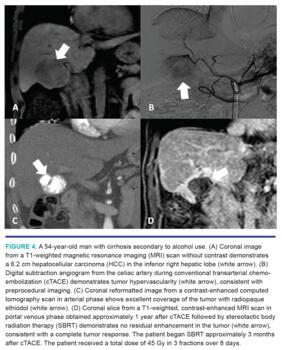

cTACE involves mixing ethidiozed oil with a chemotherapeutic agent, creating a radiopaque emulsion. After this emulsion is delivered, embolization is performed with either a gelatin foam slurry or beads. The radiopaque ethiodol is cleared by normal hepatocytes but retained by the HCC, helping the emulsion preferentially target cancerous cells. Moreover, the emulsion improves the concentrations of the chemotherapeutic agent within the target tissue (Figure 2).41 Finally, its radiopaque nature makes it an excellent target for computed-tomography guided PA (Figure 3) or SBRT (Figure 4). If PA is technically feasible for an HCC measuring 3-5 cm in size, our typical practice is to perform cTACE followed by PA, as the combination of these therapies improves oncologic outcomes.36 PA is most commonly performed either on the same day or the day following cTACE. If PA is not technically feasible or tumor size exceeds 5 cm, the radiopaque ethiodol can be used to localize the tumor for SBRT. Our institutional results demonstrated improvements in both local recurrence and overall survival in patients with unresectable HCC measuring ≥3 cm treated with TACE and SBRT versus those treated with TACE alone.42 We reserve TARE for patients with main-branch portal vein thrombus, radiation segmentectomy, and radiation lobectomy prior to surgical resection.32,33 In our practice, we primarily use glass-based spheres (TheraSphere; Boston Scientific) in patients with HCC.